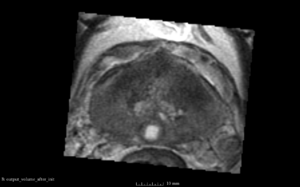

We used this sample data with Reader 1 segmentations to visually evaluate differences in the registration results. All three results of BRAINSFit with ITKv3 in Slicer 3.6 look reasonable. Using BRAINSFit with ITKv4 in Slicer 4.4 creates a reasonable result for Case 7, but look strongly distorted towards the edges of the bounding box in Case 8 and 9.

Case 8

Reference intraop volume

Reg Result Slicer 3.6 with ITKv3

Reg Result Slicer 4.4 with ITKv4